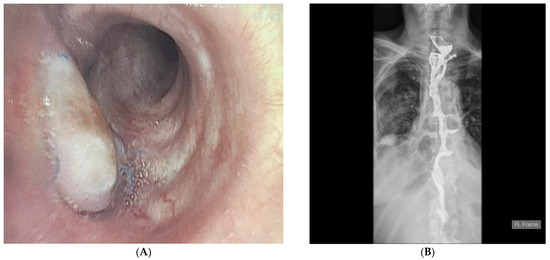

With the hope of giving this patient a better quality of life, she was admitted three months later for reconstructive surgery. Prior to surgery, bronchoscopy was performed, showing a well-vascularized flap covering the defect on the left main bronchus (Figure 4A). Retrosternal colon interposition was performed using the transversosplenic segment of the colon as a graft, with blood supply provided by the left colic artery. The postoperative course was uneventful. On the 7th postoperative day, a contrast barium study was performed, showing normal passage through the colon graft (Figure 4B). Per oral intake was then initiated.

Figure 4.

Bronchoscopy image of the flap covering the defect on the left main bronchus one month after surgery. The flap is well vascularized. The patient did not experience any respiratory symptoms after the surgery (A). Contrast X-ray study 7 days after colon interposition. The esophagocolonic anastomosis is wide; the colon graft is positioned in a linear fashion. There is no contrast leak, and the evacuation of the contrast into the stomach remnant is smooth (B).